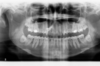

Jeune adulte traitée en technique linguale

F-Intermédiaire 2